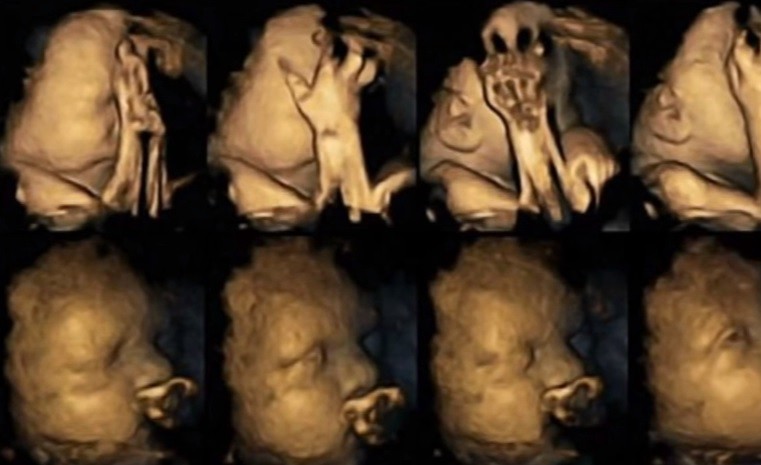

Nunca antes se había visto cómo reaccionaba el bebé en el vientre materno con tanta exactitud como muestra el último estudio realizado por la doctora Nadja Reissland, de la Universidad de Durham, publicado en Acta Paediatrica. Una alerta más para que las madres reflexionen sobre el daño que provocan en la gestación de sus hijos.

Reissland se dedicó a monitorizar las imágenes 4D de bebés de 20 madres fumadoras para compararlas con las imágenes de bebés de madres o-fumadoras.

Escaneó cómo el bebé se siente cuando la madre fuma en diferentes etapas del embarazo y las imágenes son sorprendentes y desmoralizantes: los bebés de las madres adictas al tabaco (las mujeres estudiadas fumaban hasta 14 cigarrillos diarios) hacen todo tipo de gestos y muecas de descontento y desagrado, se podría decir incluso que de dolor y estrés: se tocan la cara y la nariz mucho más, y mueven la boca con más frecuencia que los demás bebés, de gesto tranquilo.